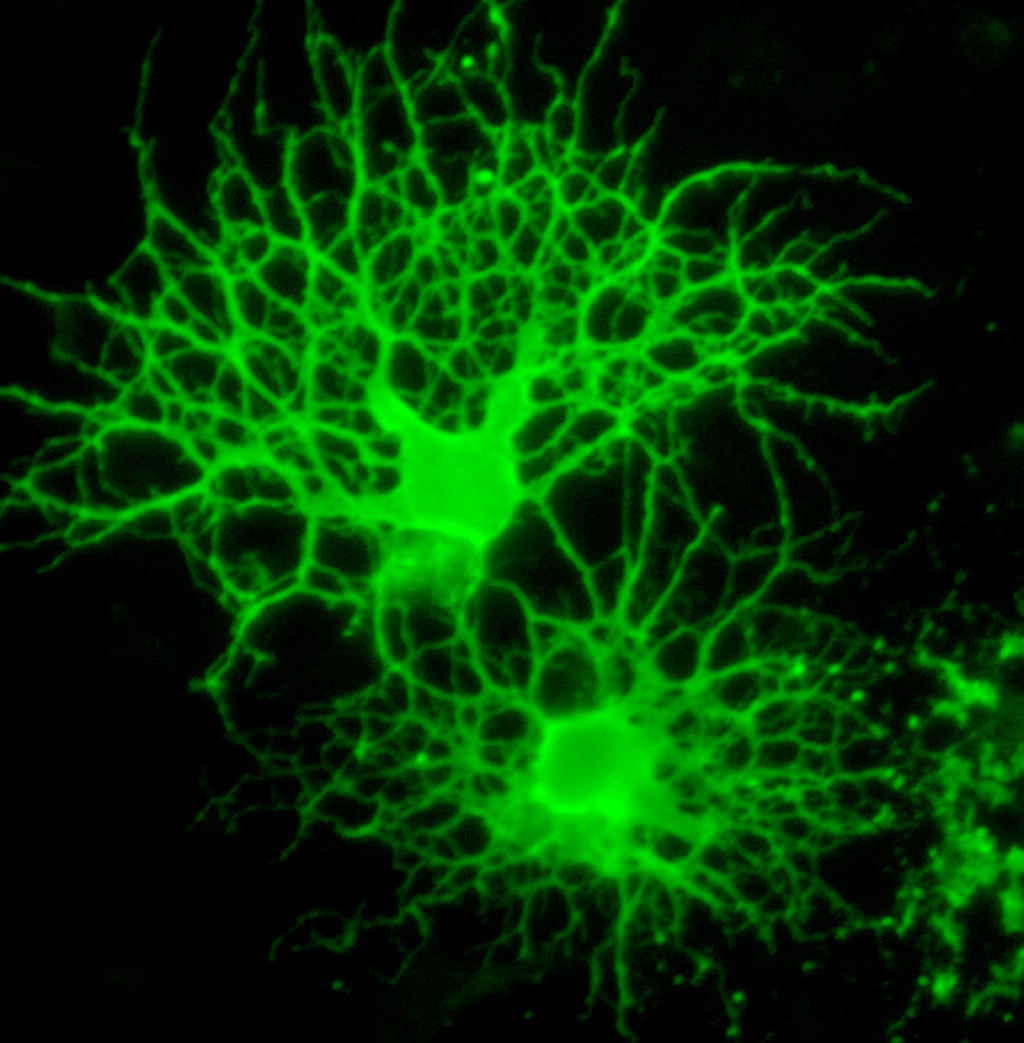

Illustrasjonsfoto: Oligodendrocytter. Science Photo Library / NTB

Myelin omgir aksonene og øker effektiviteten av impulsledning i nervesystemet. Forstyrrelser i myeliniseringen er knyttet til skader og sykdom i nervesystemet og kan forringe både sensorisk, motorisk og kognitiv funksjon. Myelin i sentralnervesystemet dannes av en bestemt type gliacelle, oligodendrocytten. En ny studie har gitt ny innsikt i hvordan en annen type gliaceller, mikrogliaceller, opprettholder normalt myelin i voksen alder (1).